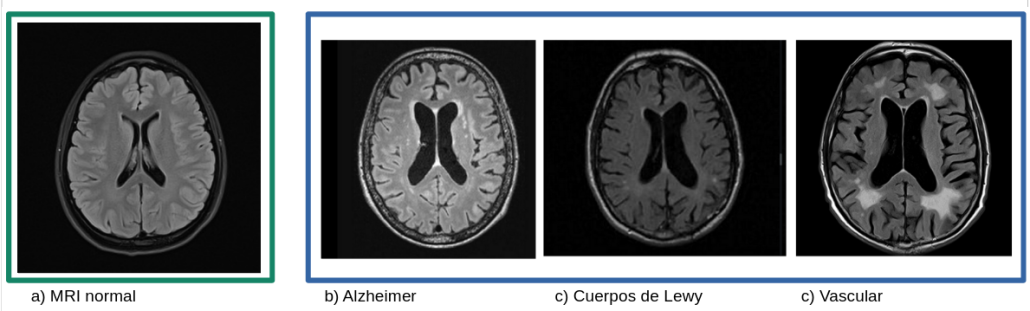

Los estadíos avanzados de muchas enfermedades neurodegenerativas comparten características desde el punto de vista clínico, anatómico y radiológico. Déficit de distintos dominios cognitivos, disminución de población neuronal, involución de masa cerebral, atrofia cortical, surcos y ventrículos cerebrales mucho más prominentes para la edad del individuo.

En la siguiente figura se compara una resonancia magnética fisiológica (a) [5] con las características radiológicas comunes en pacientes que sufren distintos tipos de demencia: Alzheimer (b) [6], demencia por cuerpos de Lewy (c) [7] y demencia vascular (e) [8]. En muchas ocasiones, los signos radiológicos se solapan, haciendo aún más complejo el diagnóstico. En este ejemplo, en la resonancia magnética del paciente con enfermedad de Alzheimer también se observan hiperintensidades periventriculares típicas de enfermedad vascular.

Comparativa de hallazgos radiológicos en demencias de distinto origen» Fuentes 5, 6, 7, 8